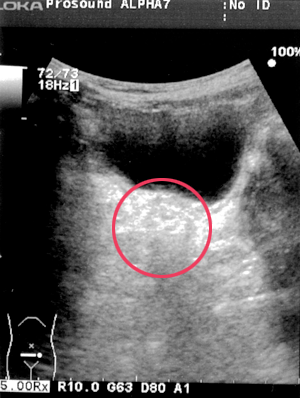

3.別人の直腸

偶発的便秘の浣腸後の直腸。径は縮小。